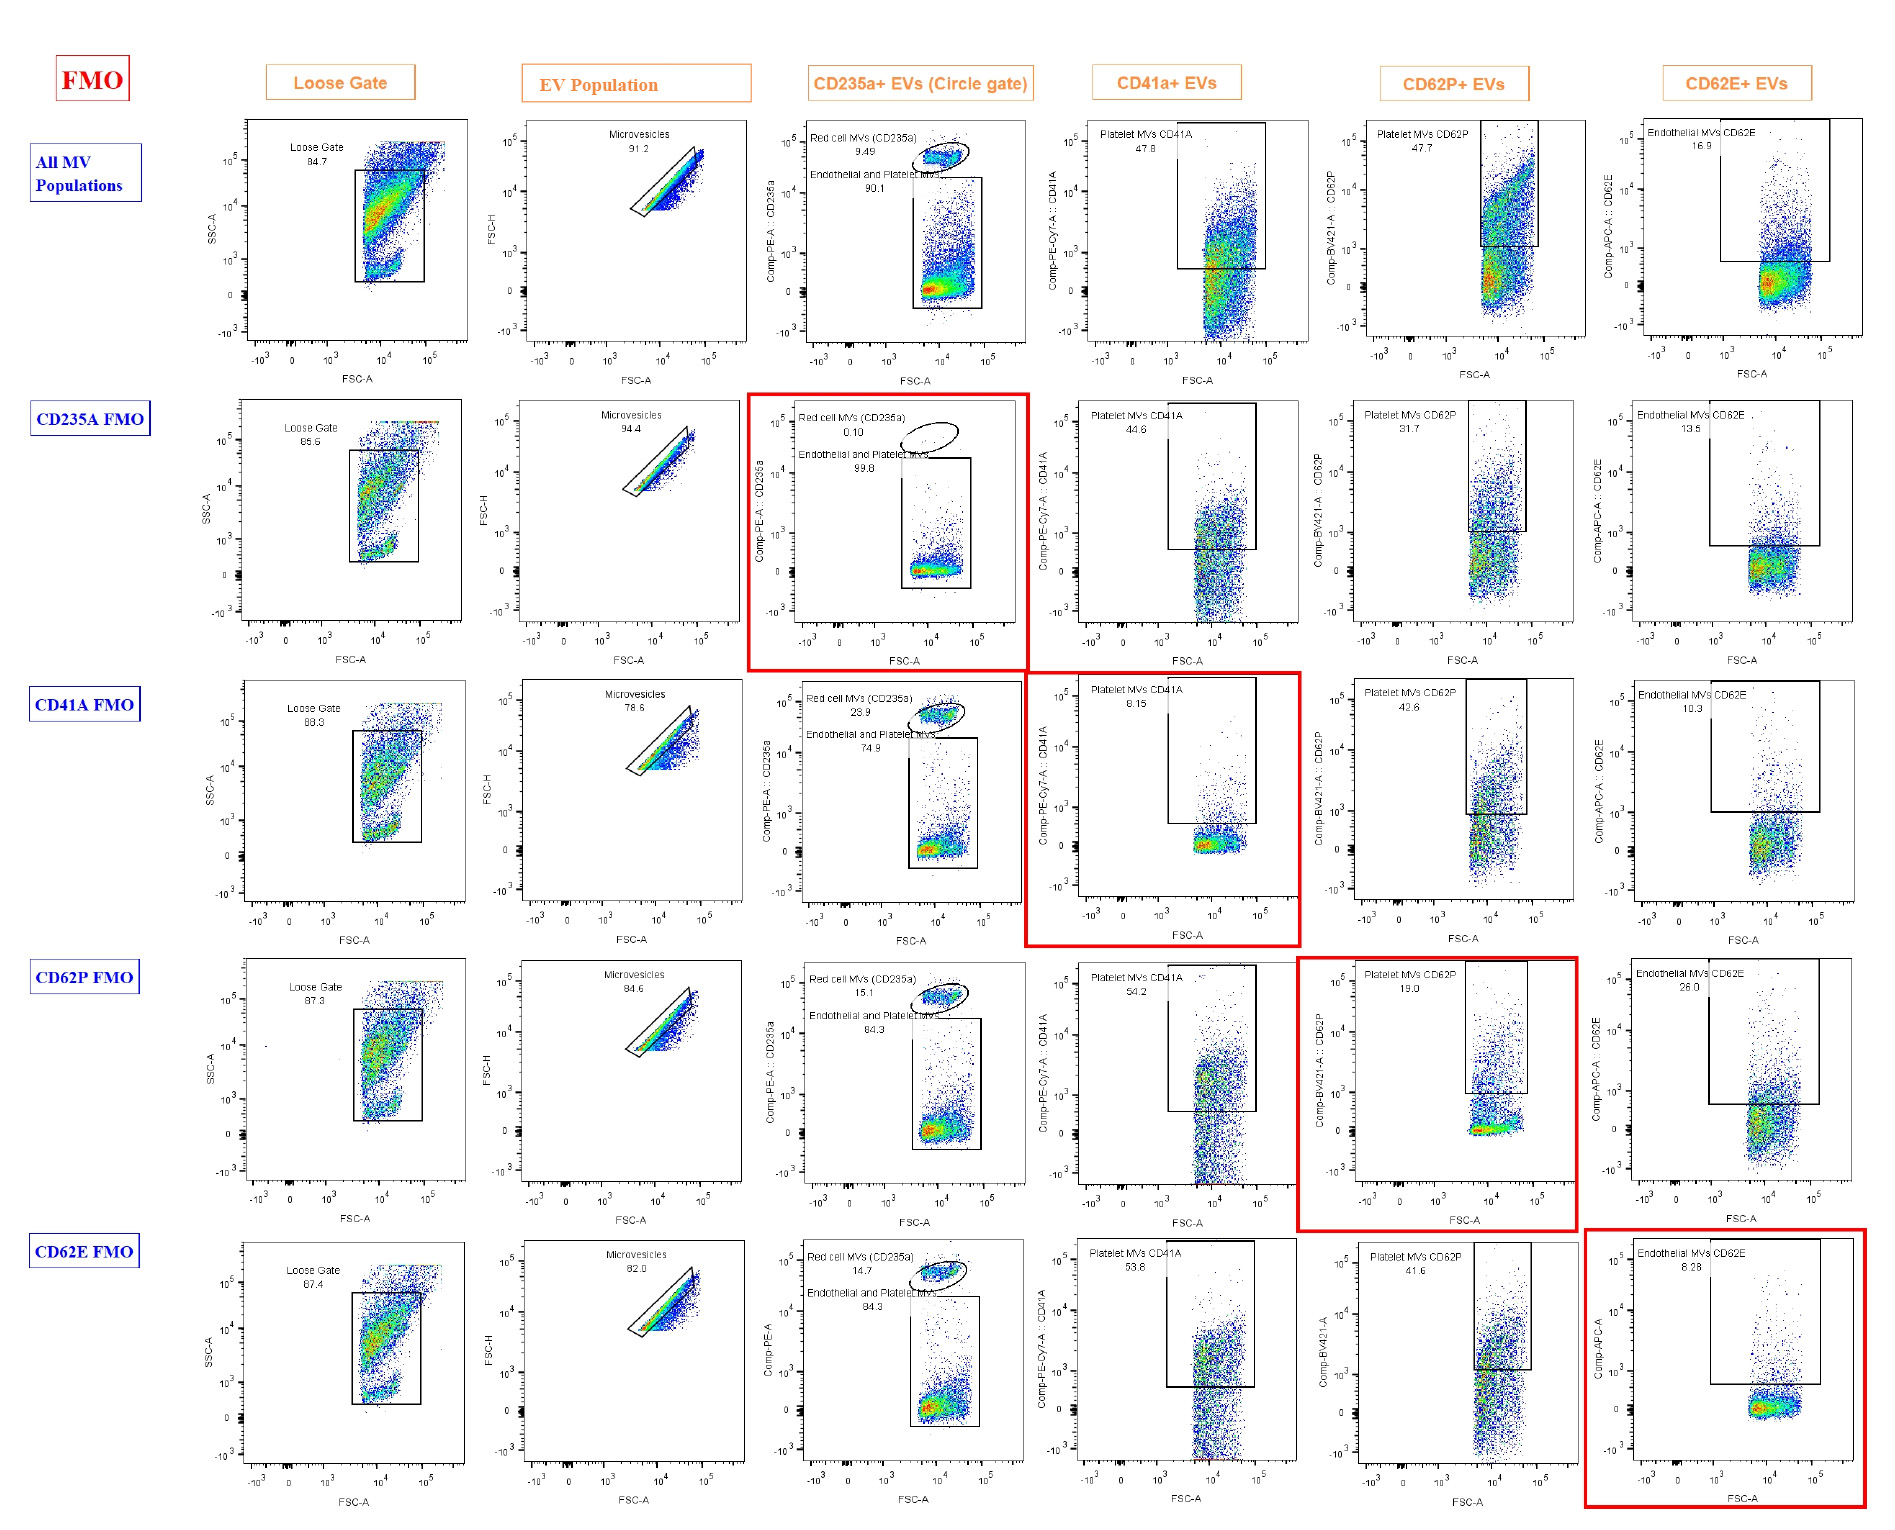

Researchers can expect well-separated populations in fluorescence histograms, with accurate identification of EV subtypes using specific surface markers. The gating strategy ensures the exclusion of debris and doublets, providing high reproducibility (Figure 3). Flow cytometry plots should reveal distinct populations of CD41a+ platelet-derived EVs, CD62E+ endothelial EVs, and CD235a+ red cell–derived EVs. The use of FMO controls aids in defining positive and negative populations. This backbone of EV analysis can be expanded to include further markers of interest.

Figure 3. Results of fluorescence-minus-one (FMO). FMO controls were used to define gating boundaries for the identification of extracellular vesicle (EV) subpopulations based on cell-specific markers. Each row represents FMO controls for a specific marker, where one fluorochrome is omitted to determine background fluorescence and set gates accurately. The first row ("All EV Populations") displays the full staining panel, used to demonstrate the overall gating strategy and EV subpopulation distribution. Subsequent rows show FMOs for CD235a, CD41a, CD62P, and CD62E, with the marker of interest omitted in each row. Gating regions were drawn using the negative populations in FMO controls (highlighted by red boxes) to accurately identify positive events in fully stained samples. EVs have a highly diverse composition, with some containing abundant proteins or internal structures. This heterogeneity results in greater variability and often higher levels of intrinsic fluorescence, which was particularly evident in the CD62P FMO. Loose gating was observed in FCS-A vs. SSC-A and in microvesicles on FSC-A vs. FSC-H. Gating for CD235a, CD41a, CD62P, and CD62E was performed on the compensated axis vs. FSC-A.